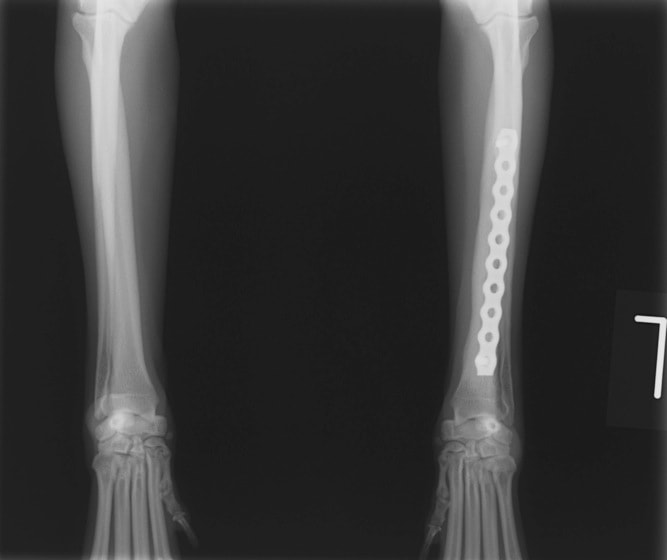

トイプードル 右遠位橈尺骨短斜骨折のALPSによる内固定

Locking Compression Plate

LCPは、スクリュー(ネジ)とプレート(金属の板)をロックする特殊な構造により骨折部位を固定する新しい世代のプレートシステムです。ひとつのホールでロッキングスクリューとスタンダードスクリューの使用を選択できるユニークな構造をしているため、骨折断端間の圧迫を目的とした従来型プレート固定法に加え、高い角度安定性を有するロッキングスクリューを用いた固定法の選択が可能です。従来のプレートシステムでは困難だった部分の骨折や癒合不全の症例に高い治療効果をもたらします。